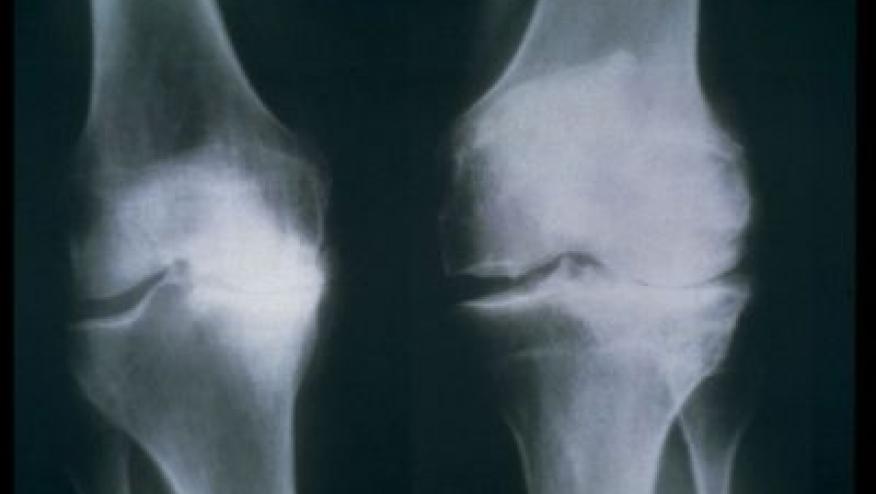

Knee replacement surgery is on the rise, and so is the cost.

According to recently released data from the Centers for Disease Control, Bloomberg reports, the rate of knee replacements nearly doubled between 2000 to 2010 (for those over 45 yrs of age). What’s more, the average age at which Americans got their knees replaced fell significantly, from 69 in 2000 to 66 in 2010. In total, there were over five million knee replacement surgeries performed during the decade.

The aging of society and increasing prevalence of obesity is driving most of this osteoarthritis related surgery. In the UK, the National Health service estimates that half of all knee and hip replacements are due to obesity.